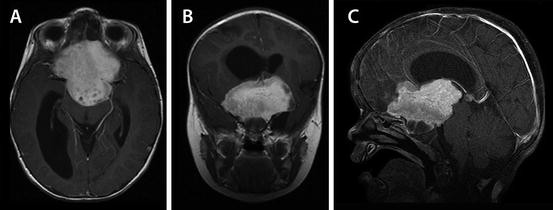

Li Fraumeni Syndrome Multiple Distinct Brain Tumours In Two Brothers Sciencedirect